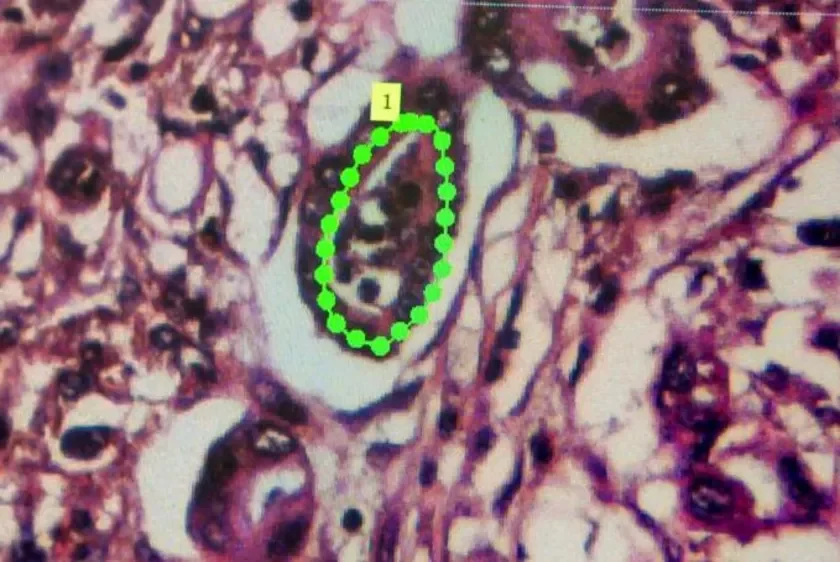

В течение 6 месяцев ученые трижды проводили иммунологический анализ крови.

У всех десяти пациентов в результате вакцинации не выявили каких-либо серьезных побочных эффектов и осложнений, а имуномаркеры крови показали, что вакцина активировала специфические противоопухолевые иммунные клетки.